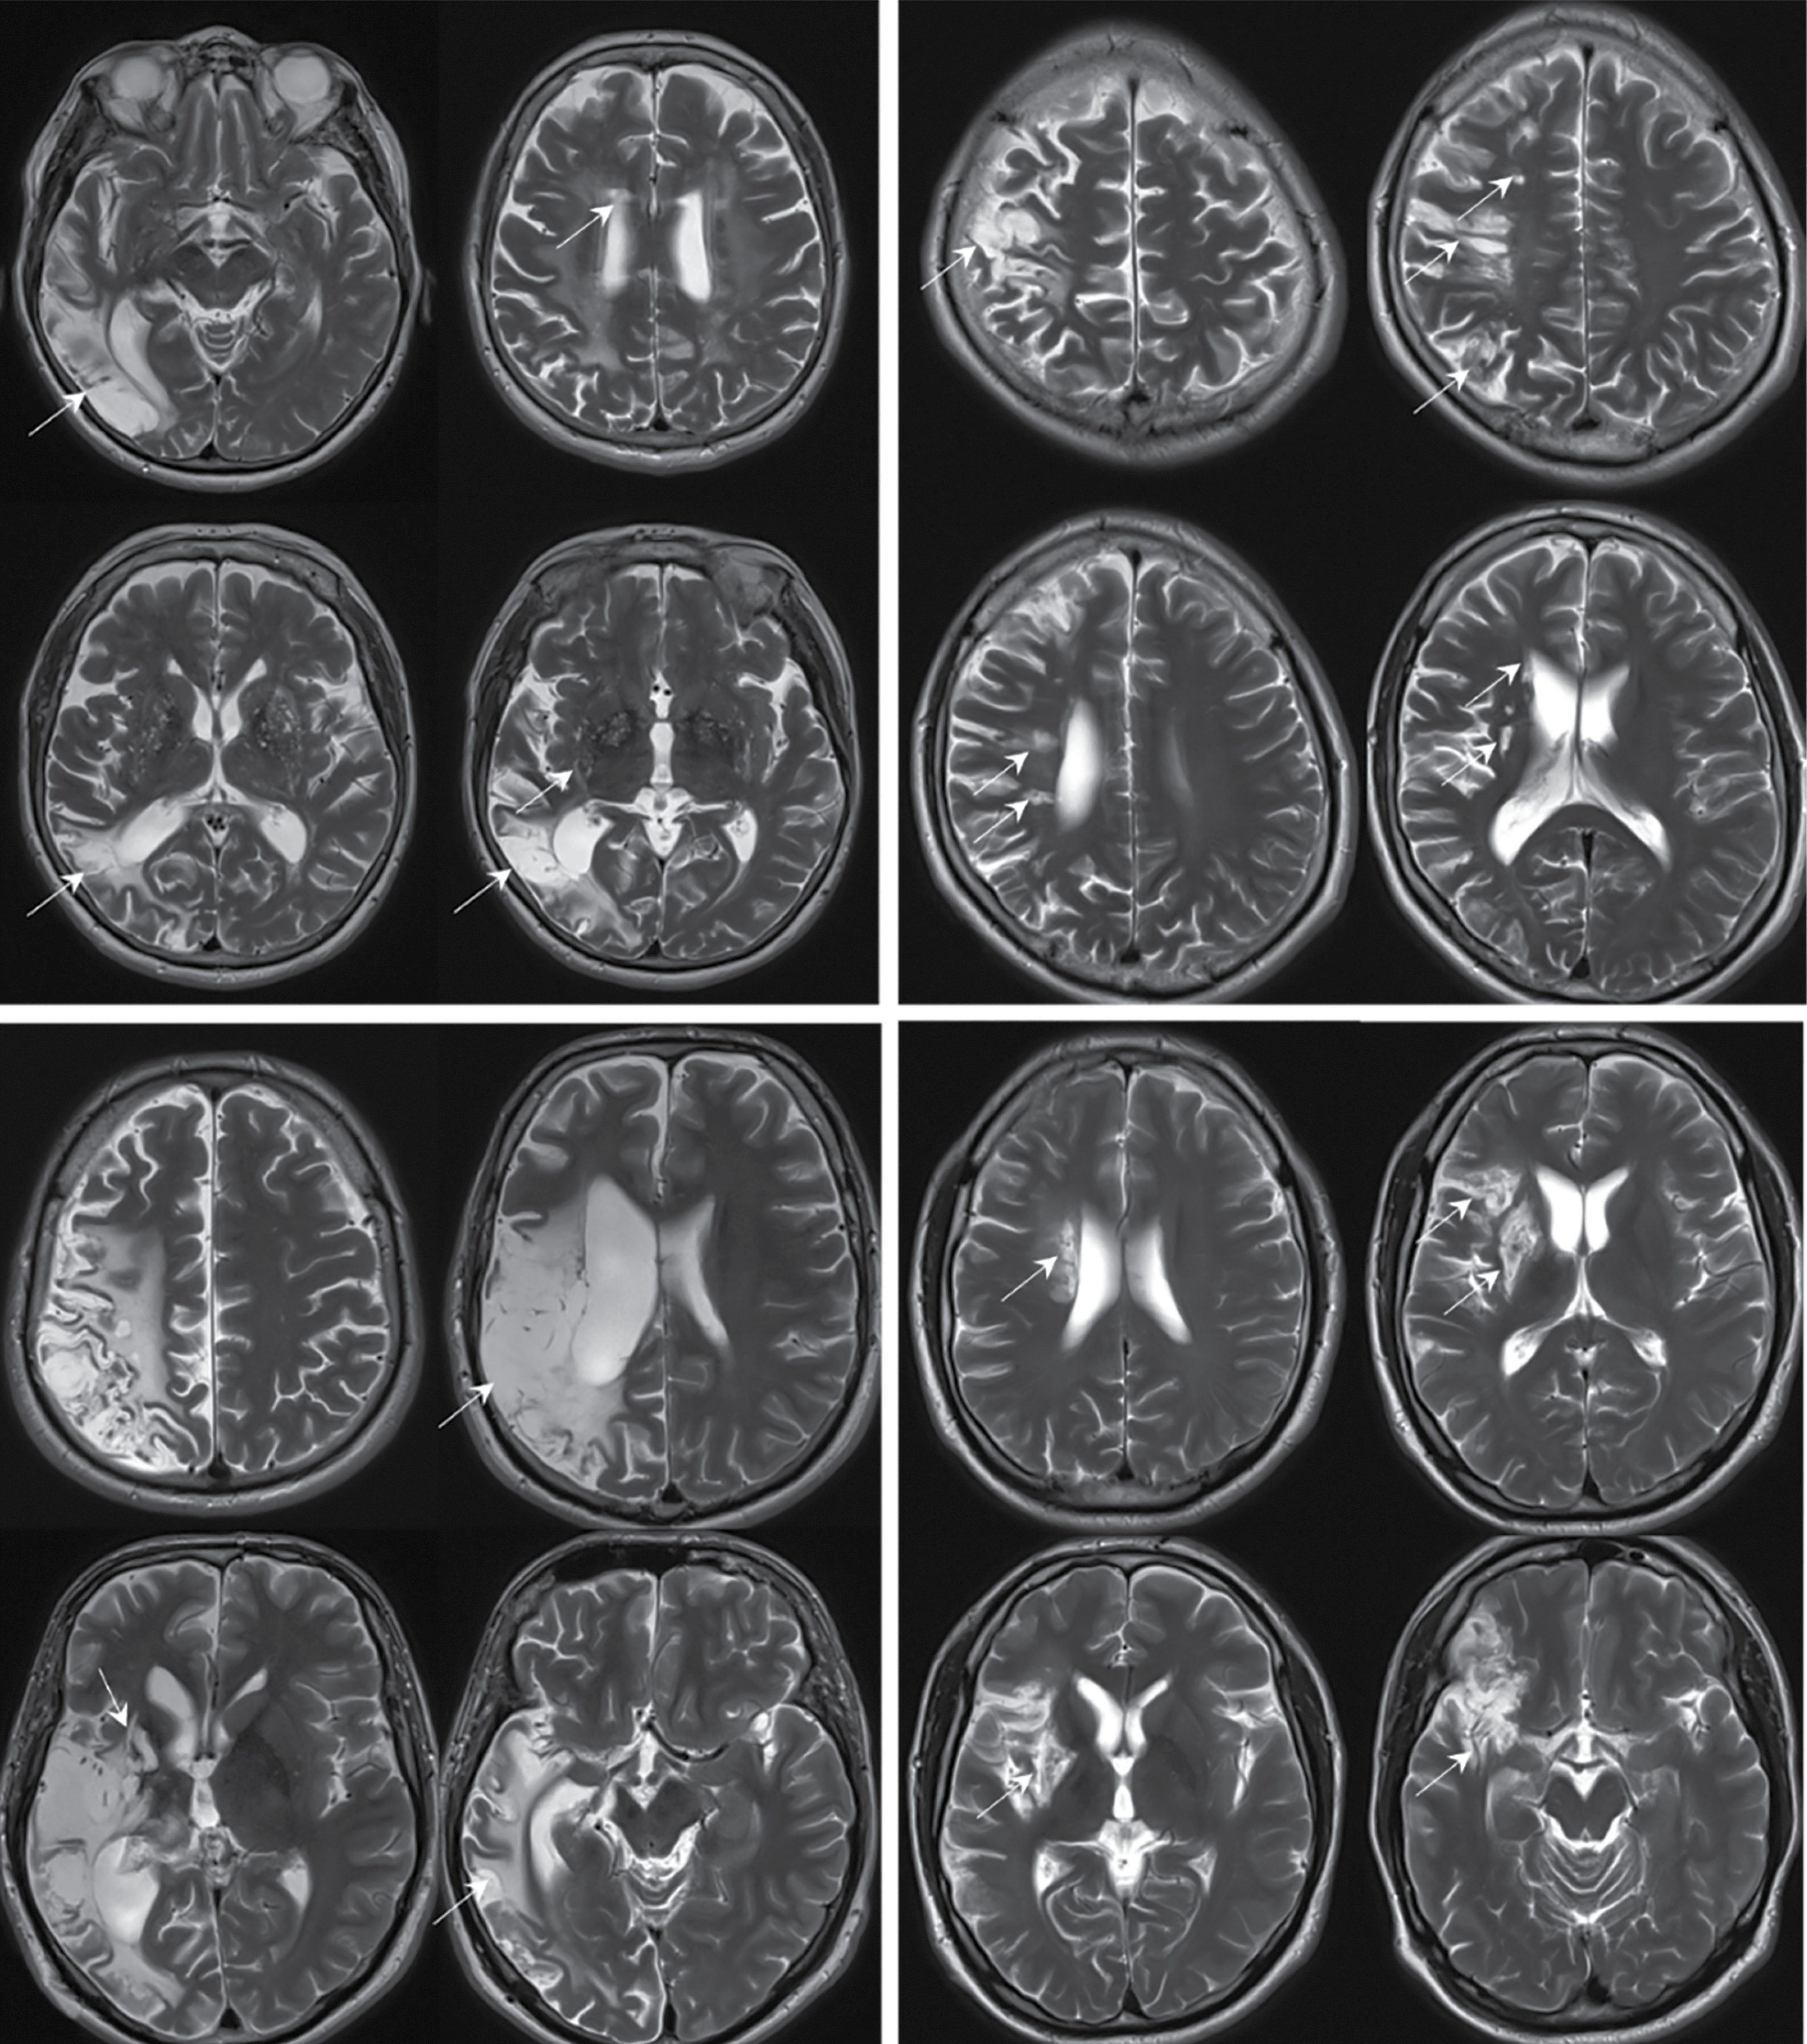

Рис. 3. МРТ головного мозга пациентов с ИП в аксиальной проекции в режимах Т2 (A–D) и ДВИ с b-фактором 1000 с/мм2 (E).

Визуализируются два основных паттерна поражения: небольшие постинфарктные очаги в глубоком белом веществе, базальных ганглиях и стволе мозга (A, B), у 1 пациентки обнаружены очаги острой ишемии в левом полушарии мозжечка (E); крупные корковые постинфарктные изменения в бассейне средней мозговой артерии и зонах смежного кровоснабжения без вовлечения базальных ядер (C, D); постинфарктные изменения (A–D) и очаги острой ишемии (E) указаны стрелками.

Fig. 3. Brain MRI of patients with PV in axial T2 (A—D) and DWI sequences with a b-value of 1,000 s/mm2 (E).

Two main involvement patterns are visualized: small post-infarction lesions in the deep white matter, basal ganglia, and brainstem (A, B); one patient had lesions of acute ischemia in the left cerebellar hemisphere (E); large cortical post-infarction changes in the middle cerebral artery system and adjacent perfusion territories without basal ganglia involvement (C, D); post-infarction changes (A–D) and acute ischemic lesions (E) are indicated by arrows.

Истинная полицитемия

Характерными клинико-нейровизуализационными признаками НМК при ИП являлись инфаркты корковой локализации в зонах смежного кровообращения, стволе, мозжечке, соответствовавшие перенесённым НМК по типу гемореологической микроокклюзии с частотой встречаемости 65%. При ретроспективной оценке клиническая картина была представлена неспецифическими жалобами на головокружение, иногда рвоту, общую слабость, в связи с чем пациенты думали в первую очередь о пищевом отравлении или, в случае отсутствия рвоты, об ухудшении течения основного гематологического заболевания, зачастую не обращаясь за медицинской помощью. В 40% случаев постинфарктные изменения в веществе головного мозга встречались в бассейне вертебрально-базилярной системы, в 60% — в каротидной или зонах смежного кровоснабжения. У 3 пациентов выявлена тромботическая окклюзия магистральных артерий головы с последующим развитием НМК (2 пациента с тромбозом одной из позвоночных артерий, 1 пациент с тромбозом внутренней сонной артерии), при дополнительном исследовании МРТ головного мозга (в режиме Fat Sat) не было получено данных о наличии диссекции сосудов.

При нейровизуализации основные находки у пациентов с НМК на фоне ИП были представлены в виде двух паттернов (рис. 3):

- небольшие (до 1,5 см) постинфарктные очаги в стволе, мозжечке, глубоком белом веществе и базальных ядрах, корковые постинфарктные зоны, кистозно-глио-зные изменения без вовлечения в процесс базальных ядер, в том числе в зонах смежного кровоснабжения, вероятно, после НМК по типу гемореологической микроокклюзии;

- крупные корковые постинфарктные изменения в бассейне средней мозговой артерии и зонах смежного кровоснабжения без вовлечения базальных ядер.